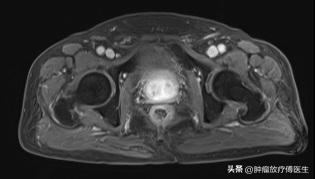

2017-2-8放射治疗1年半后复查盆腔MRI

2014年12月患者PSA呈持续性升高,经多方打听之下,就诊我科,2015年8月7日PSA升高至1.08ng/ml,睾酮16.74ng/dl。复查盆腔MRI示:前列腺7点方向结节影,考虑前列腺癌。全脊柱MRI示未见转移。考虑内分泌治疗后出现去势抵抗,2015年8月24日给予前列腺癌根治性调强适形放射治疗,考虑患者病灶局限于前列腺内,80岁高龄,为提高生活质量,不予盆腔预防照射,不良反应轻,靶区包括前列腺及双侧精囊,肿瘤照射剂量 72Gy/1.8Gy/40f。放射治疗过程予以“注射用醋酸亮丙瑞林3.75mg皮下注射1/4周+比卡鲁胺50mg口服1次/日”联合内分泌治疗。放射治疗结束复查PSA 1.620ng/ml,此后定期复查,病情稳定,继续内分泌治疗。2016年3月复查PSA0.27ng/ml ,2016年12月复查PSA 0.64ng/ml 。